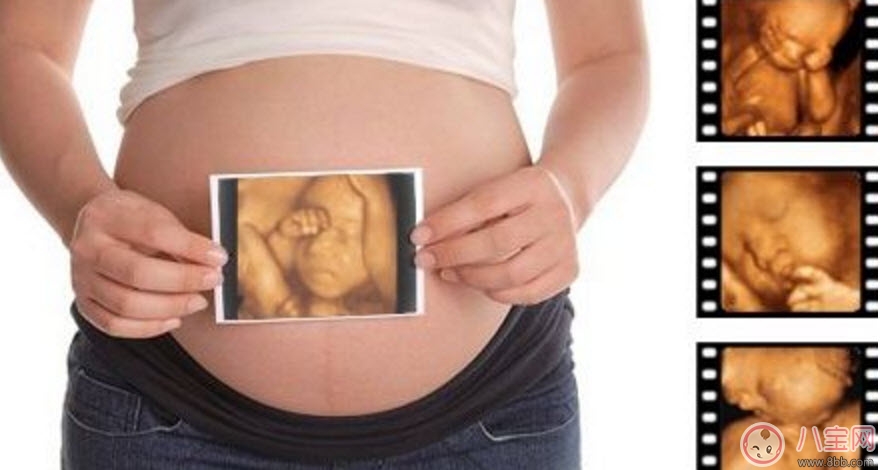

孕婦的羊水適量的話就可以做這項檢查。但是受胎兒體位、胎盤以及孕期不同等方面的因素影響,專家建議最佳做四維彩超的時間應該是12-30周,這個時期就可以完全獲取到胎兒的面部以及身體等結構的圖像。懷孕十個月的時候里最少要做3次的四維彩超,時常觀察胎兒成長。

1、一般整個孕期做三次四維彩超,懷孕的22~26周做四維彩超最佳,但是具體時間也是因人而異的。

4、胎兒是否畸形:彩超檢查時發(fā)現(xiàn)胎兒畸形的一個重要的手段。一旦發(fā)現(xiàn)胎兒畸形,就可以及時終止妊娠,通常孕婦在妊娠22-26周做彩超可以篩查胎兒是否畸形,因為這個時段的胎兒各個器官都已經(jīng)發(fā)育成型形,比較容易看出有沒有畸形。所以做彩超檢查十分重要。